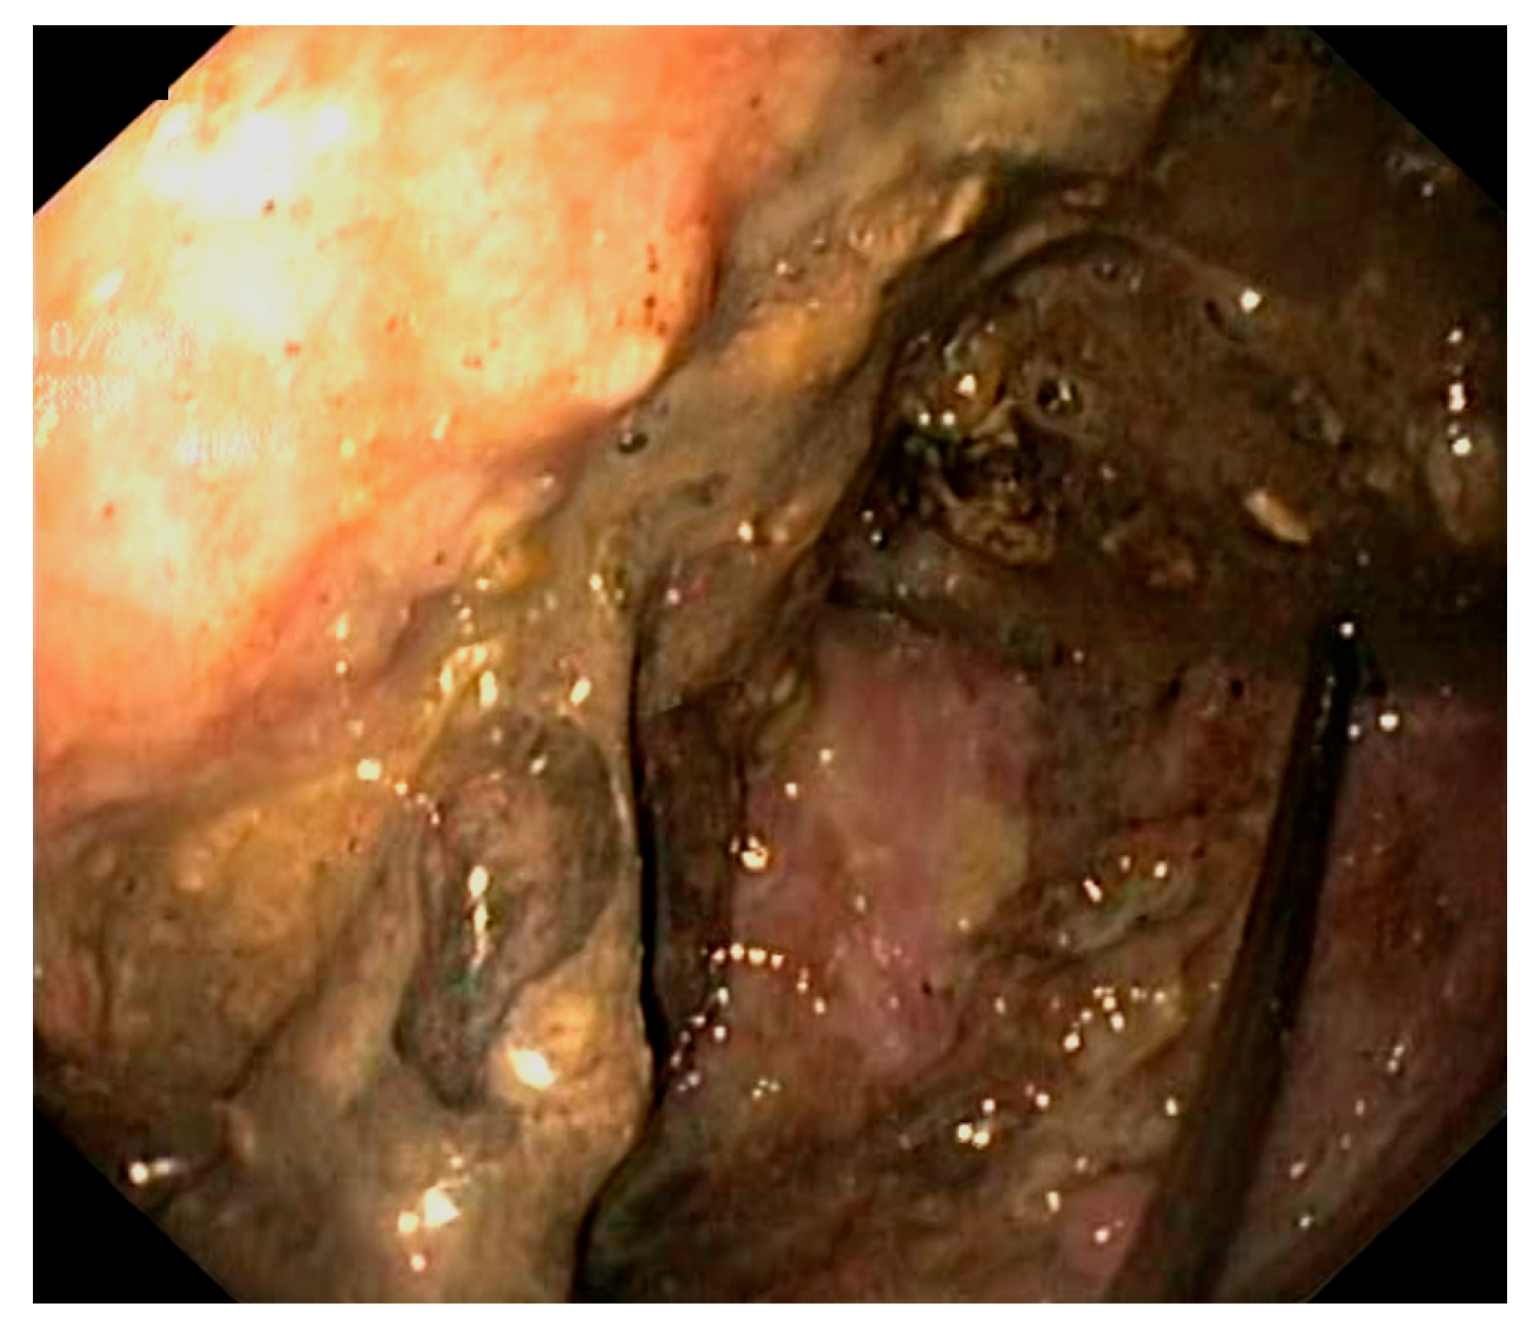

2. Detailed Case Description

2.2. Results